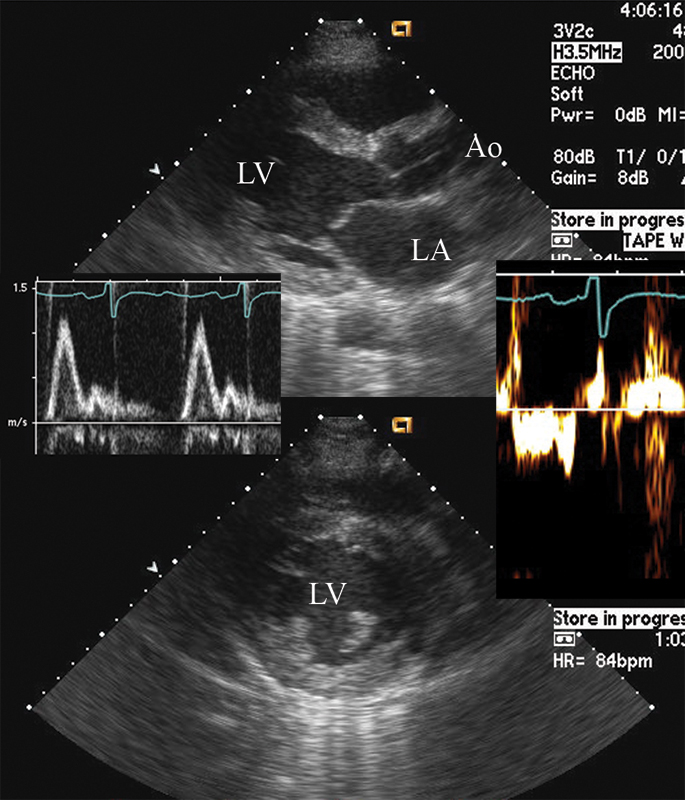

فحوصات تشخيصية لبعض امراض القلب والشرايين التاجية